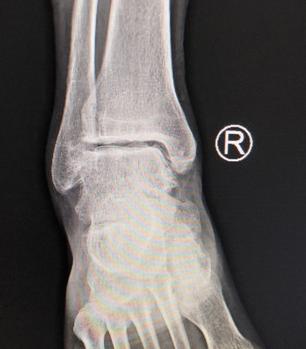

踝关节炎,跟骨骨折术后疼痛,这种情况没有合适的药物、也没必要去做手术时,但又疼痛难忍,此时,玻璃酸钠便是很好的选择。

“之前有踝关节骨折术后的患者,一般来说,术后一年左右走路的话,还是会有稍微疼痛不适,但是给他用完玻璃酸钠之后效果就非常明显,还有一个是跟骨骨折术后,也给他打了一支玻璃酸钠,也是打完之后效果明确,走路疼痛明显地缓解了。关于玻璃酸钠的疗效,上海华山医院做过一个研究,玻璃酸钠对于关节疼痛有长期疗效,玻璃酸钠注射后5—13周,患者疼痛改善11%—54%。”